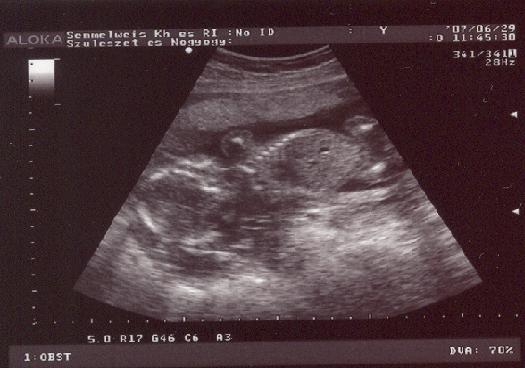

Lafie! Fiú vagy lány, de nagyon kis aranyos